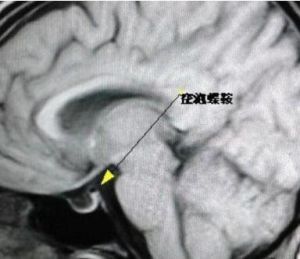

空泡蝶鞍蝶骨在顱中窩中間部分高起,形如馬鞍的骨結構。蝶鞍中央凹陷叫垂體窩,容納腦垂體。正常情況下,蝶鞍與腦垂體之間緊密相貼,幾乎沒有空隙。當各種病理因素導致蝶鞍...

流行病學 病因 發病機制 臨床表現 診斷蝶鞍是顱內骨結構的解剖學名稱,指的是蝶骨在顱中窩中間部分高起,形如馬鞍的骨結構。 蝶鞍中央凹陷叫垂體窩,容納腦垂體。 正常情況下,蝶鞍與腦垂體之間緊密相...